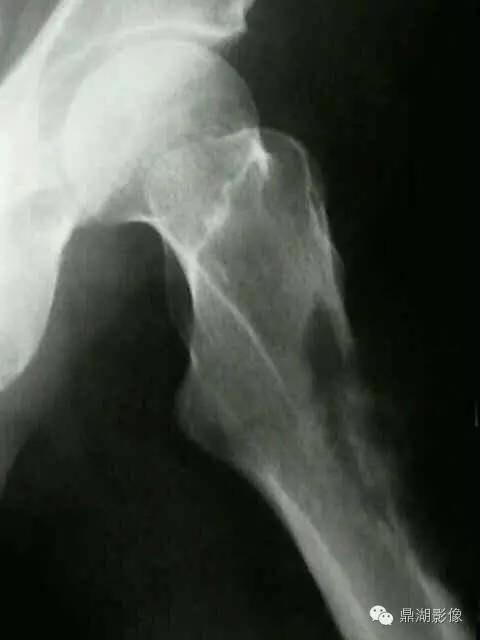

70岁,男,前列腺癌患者

X线片表现:成骨性转移表现为在骨外型没有改变的骨背景上出现圆形或椭圆形致密影,有时呈地图状,边缘不规则,多数病灶可融合成片,也有病灶累及大部分或整个骨,有时在成骨性病灶边缘散在少量溶骨性破坏。密度呈棉絮样增高。前列腺癌骨转移多较典型,结合临床,诊断一般不难。

实验室检查,血清碱性磷酸酶常增高,约占80%~85%;血清酸性磷酸酶也明显增高,对诊断前列腺癌骨转移有重要价值。